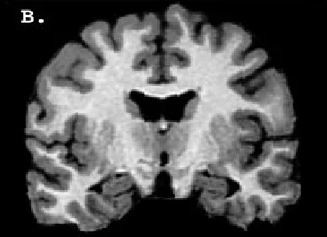

Amerika'nın Kentucky eyaletinde yaşayan bir kadın, beyninin Amigala kısmında yer alan genetik bir bozukluk nedeniyle korku duygusuna sahip değil.

İlk olarak 1994 yılında tıp literatürüne giren bu rahatsızlığın genel ismi Urbach-Wiethe.